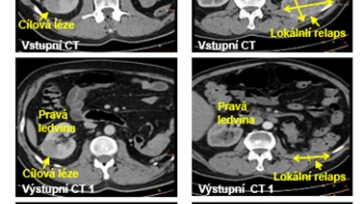

Česká protirakovinová látka MitoTam v liečbe nádorov účinkuje

Výskumný tím pod vedením profesora Jiřího Neužila z Biotechnologického ústavu AV ČR v centre BIOCEV popísal na nádoroch ľadvín účinok českej protirakovinovej…